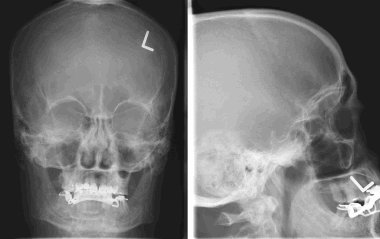

В большинстве случаев обзорная рентгенография черепа не обладает диагностической ценностью, поскольку не позволяет получить никаких данных, которые могли бы указывать на наличие менингиомы. Иногда могут отмечаться кальцифицированные участки или зоны реактивного гиперостоза. В редких случаях могут быть видны участки остеолиза.

8. На рентгеновском снимке во фронтальной плоскости хорошо заметно кальцифицированное образование в области лобной пазухи. На снимке в латеральной проекции образование визуализируется кверху от решетчатой пластинки. Несмотря на то, что по результатам исследования можно заподозрить, обнаруженные признаки неспецифичны, и поэтому обнаруженное внутричерепное образование требует дообследования при помощи КТ.

Большинство рентгеновских снимков не отображают признаков наличия заболевания. Менингиомы типа en plaque характеризуются диффузным гиперостозом, чаще в области крыла клиновидной кости и птериона. Такие результаты исследования с большой долей вероятности свидетельствуют о наличии

болезни.

Кальцинаты внутри опухоли являются значительно более редким рентгенографическим проявлением менингиомы; это зачастую приводит к ложно-отрицательным результатам. Большинству пациентов не проводится рентгенографическое исследование, поскольку диагноз был подтвержден при помощи КТ или МРТ.